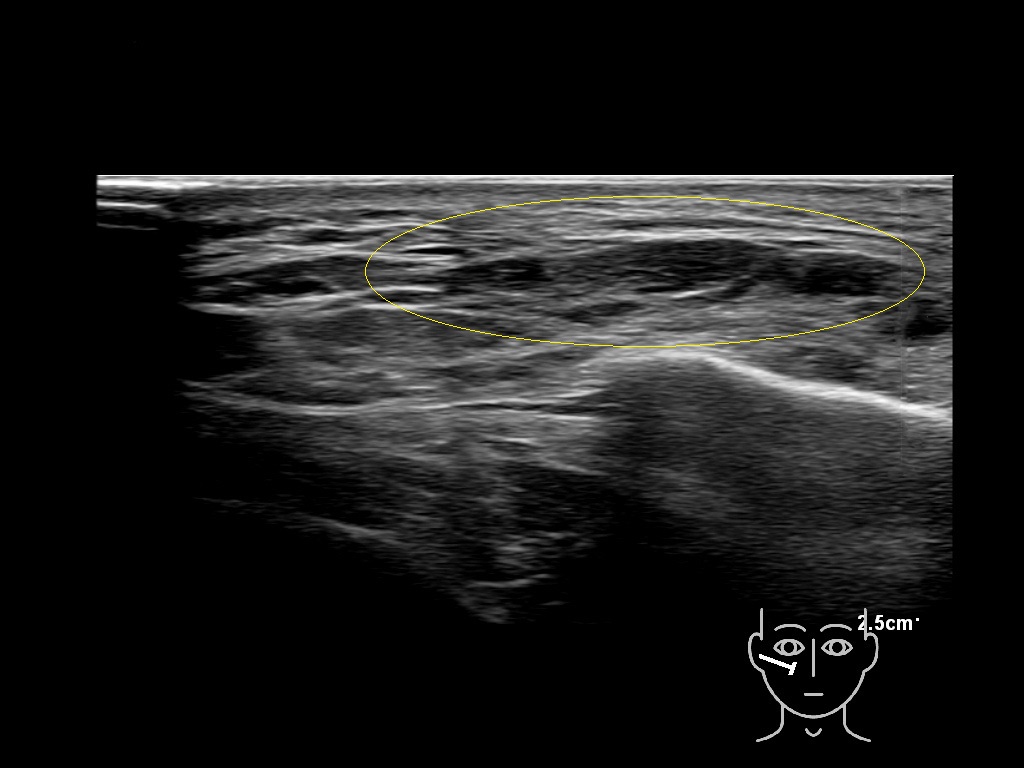

Fascia

Filler deposits may end up unintentionally in the SMAS or fascial layers of the skin. Very often this will not lead to adverse events, however, adverse events ( nodules, migration / redistribution impaired muscle movement and smiling and malar edema) are are often related to filler ending up in the SMAS or fascia.

Study the first image to recognize the different layers. If you are sure about the layers, swipe to the second image to view the answer (if applicable).